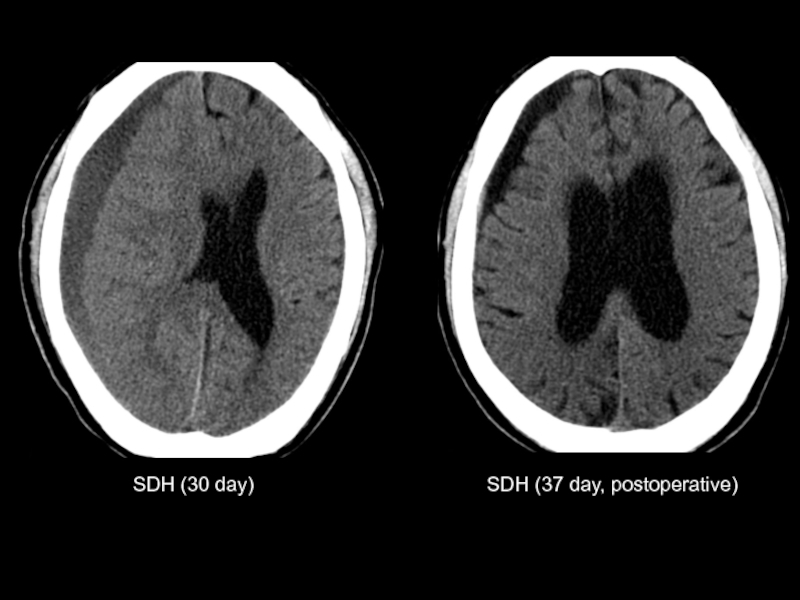

SDH (30 day)

SDH (37 day, postoperative)